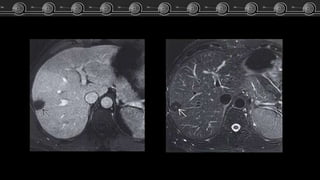

Hemangiomas

Cavernosos

• T1:

hipointensos o isointensos con

respecto a la sangre.

RM

• T2:

Hiperintensos.

• T1 + C:

Igual patrón de captación que

en la TC.